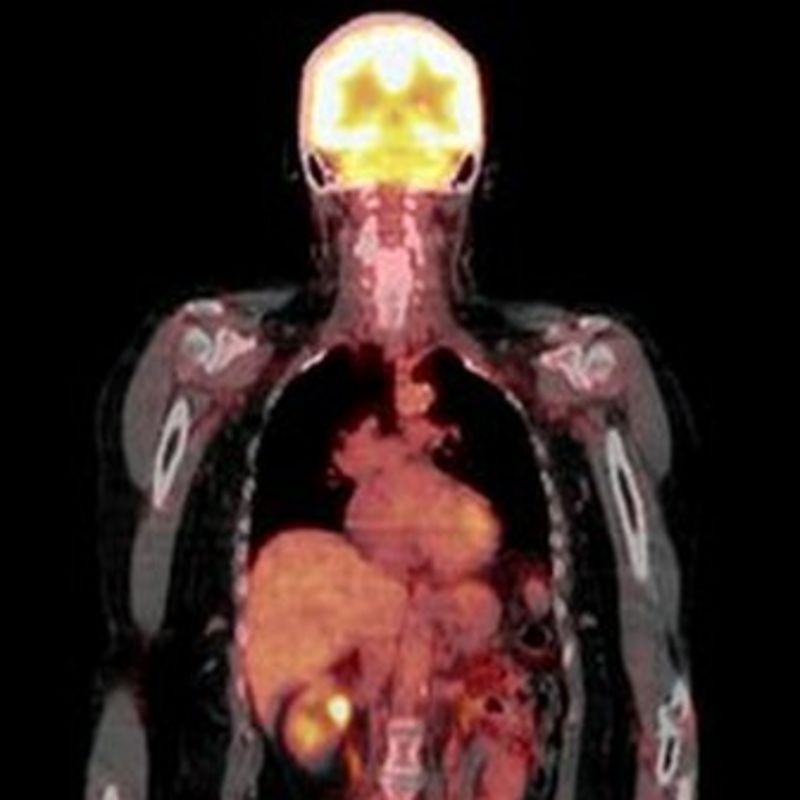

Quintessential PET scan does not detect cancer cells.

Quintessential PET scan does not detect cancer cells. What Imaging Is Used To Detect Cancer doctors use imaging tests to take pictures of the inside of your body. doctors use imaging tests to make pictures (images) of the inside of your body. imaging tests used in diagnosing cancer may include a computerized tomography (ct) scan, bone. Screening mammography has been shown to reduce deaths from breast cancer. Imaging tests can be used. What Imaging Is Used To Detect Cancer.